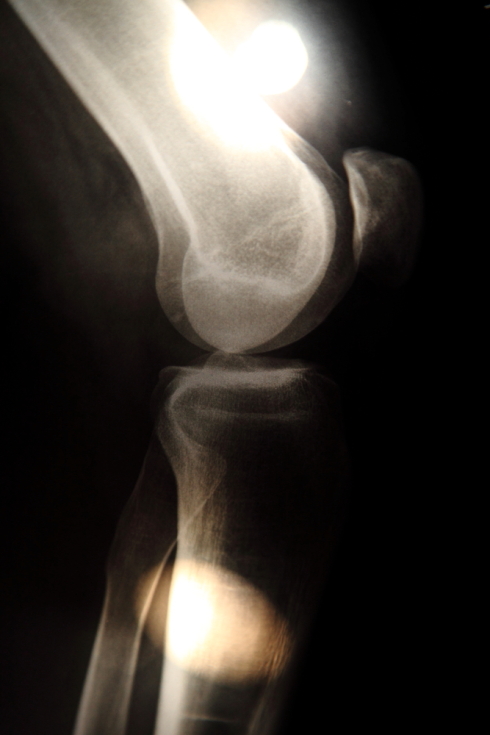

Photo works